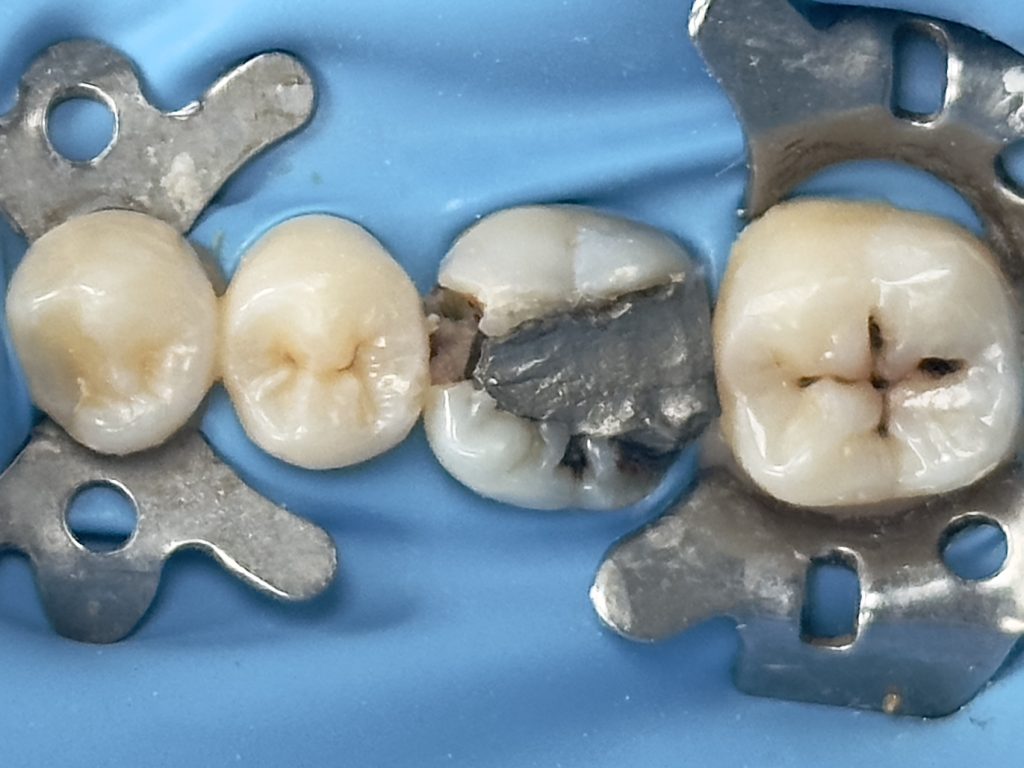

1st visit :-

-Complete amalgam removal

-gingival trimming of the inflamed gingival caused by over hanging margin

-clean & neat margin

-IDS & RC

-DME (matrix sealed with teflon &diamond wedge)

-ever X posterior to increase fracture resistance